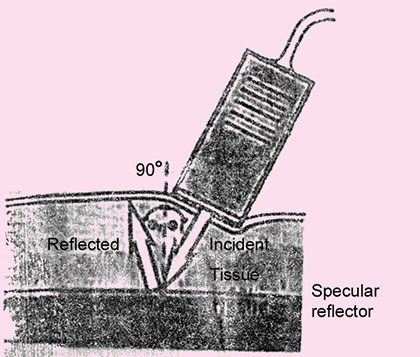

Reflection is the return of incident ultrasound energy as an echo directly back to the transducer when 3interacting with boundary at normal incidence. Reflection occurs at the interface between two dissimilar materials (Figs 1.3A and B).

Angle of incidence The angle of incidence is equal to angle of reflection. These angles are defined relative to a line drawn perpendicular to the surface of interface.

Amount of reflection is determined by angle of incidence. Higher the angle of incidence, less the amount of reflected sound wave.

Specular reflector Specular reflectors are those which reflects the ultrasound energy very efficiently as mirror reflect light.

The specular reflectors are smooth and continuous and their boundaries are large in comparison with the incident ultrasound wave length, e.g. the walls of vessels or tissue membrane, fetal skull, diaphragm, etc. Depending on angle at which ultrasound meets the refelector, it can reflect all or part of the beam.

For specular reflector, transducer must be positioned so that generated sound beam strikes the interface perpendicularly. This is known as perpendicular incidence (Fig. 1.4).

Fig. 1.3A: Specular echo. The figure represents what happens when an ultrasound beam interacts with an acoustic boundary (i.e. where medium I and medium II have different acoustic impedances). Note that under these circumstances, the beam strikes the boundary at a 90-degree angle. This results in an undeviated transmitted beam and a reflected beam, which is called a specular echo

If this beam is not perpendicular to the surface of interface this is known as oblique incidence. So even if there is specular reflector reflecting the ultrasound wave very efficiently but reflected portion of ultrasound wave will be going in the some direction and therefore will not be received by the transducer because same transducer is used both to transmit and to receive ultrasound and almost no reflective wave will be detected by transducer if ultrasound beam strikes the patient surface at angle more than 3° from perpendicular (Fig. 1.5).

Fig. 1.4: Large flat surface act as mirror-like (specular) reflectors, sending large amounts of sound back to the transducer

Fig. 1.5: Sound reflected from interface between tissue 1 and tissue 2 will not be detected because the transducer is too far from perpendicular